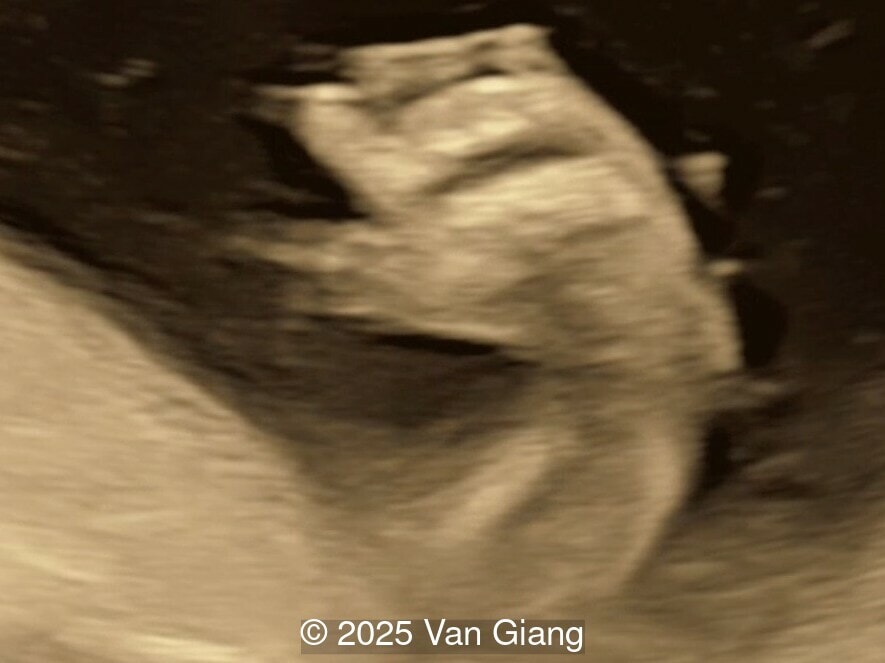

A 32-year-old primigravida presents at 20 weeks gestation without first trimester screening. Ultrasound reveals a small for gestational age fetus with the following anomalies:

Ultrasound revealed severe mandibular and zygomatic hypoplasia, glossoptosis, cleft palate, and micrognathia with an abnormal facial profile. Both upper limbs showed radial ray sequence with abnormal thumbs and shortened forearms. Unilateral clubfoot was also noted. No major cardiac or visceral anomalies were observed. Based on these findings, Nager syndrome was suspected.

Right hand

Image 3 Right hand